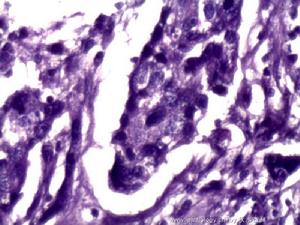

2.組織病理學檢查 術前應儘可能用其他方法作出診斷,如有必要,可行剖腹探查或腹腔鏡手術取活組織病理學檢查。